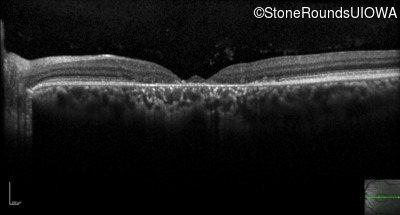

Optical Coherence Tomography - Right - 20/100 +1

Exemplar / OCT Stack

Optical Coherence Tomography - Right - 20/80 -1

Optical Coherence Tomography - Right - 20/100